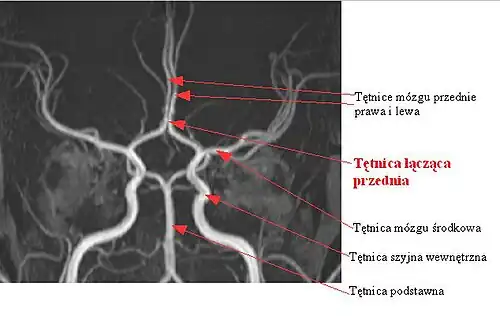

Tętnica łącząca przednia

Tętnica łącząca przednia (łac. arteria communicans anterior) – w anatomii człowieka tętnica łącząca dwie (prawą i lewą) tętnice przednie mózgu. Topograficznie znajduje się ona w dole przednim czaszki, do przodu i ku górze od skrzyżowania wzrokowego, u wejścia do szczeliny podłużnej mózgu[1][2][3].

Jest to naczynie krótkie, o długości przeciętnie około 4 mm i dużej zmienności osobniczej – u wielu ludzi stwierdza się brak tętnicy łączącej przedniej. Może być ona też tak krótka, że tętnice przednie mózgu praktycznie stykają się ze sobą[1]. Niewykształcenie się tętnicy łączącej przedniej najczęściej nie daje objawów klinicznych i jest wykrywane przypadkowo. Tętnica łącząca przednia wchodzi w skład koła tętniczego mózgu i w razie jej braku koło to traci swą ciągłość.